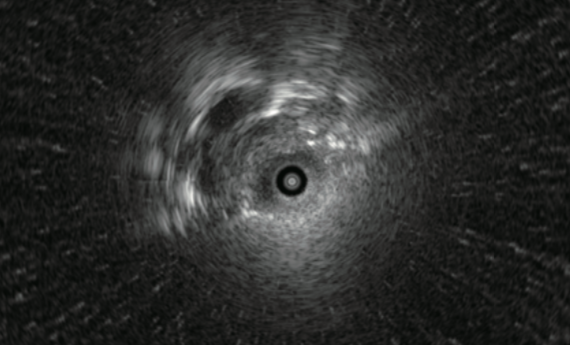

■ The tip of the probe should be carefully adjusted to observe the the maximum diameter of the lesion under the ultrasound image.

Center of lesion

Edge of lesion